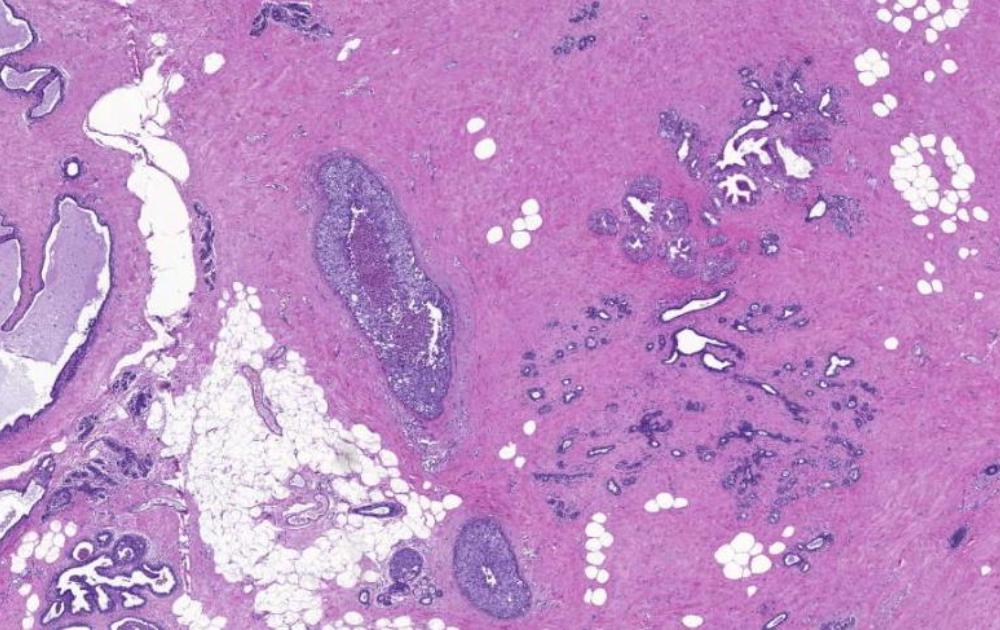

Diagnose?

Barettmetaplasie (dunkelviolett = mit Dysplasie)

Durch Reflux -> Metaplasie (nicht maligne) der Epithelien, intestinalisiertes Epithel/ Becherzellen, Biopsate mit Plattenepithel und Zylinderepithel (nur dann weiß man es ist Übergangsbereich)

Barrett-Zelle = Becherzelle